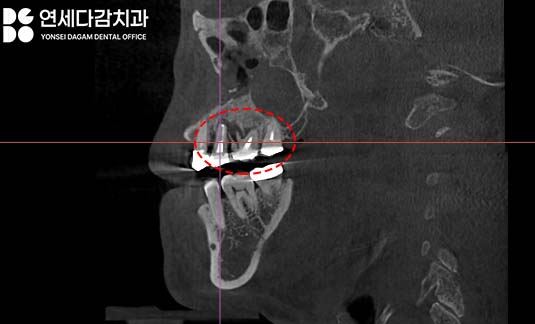

따라서 이러 경우 CT 분석을 통해

사용할 수 있는 뼈를 미리 정확히 확인하고,

송파구 치과 에서는 이렇게 다양한 각도로

3차원적으로 구조를 살펴보며

염증의 범위를 살펴봅니다.

또한 결손 부위를 피해 가능한

건강한 골조직에 위치하도록

신중하게 각도와 깊이를 계획하고,

적절한 크기와 길이의

인공 치근(Fixture)을 선택하였습니다.

면밀한 분석 후

우선 문제가 되고 있던

어금니들을 발치했습니다.

이후 염증을 꼼꼼하게 없애기 위한

배농 작업을 시행했습니다.

그 후 소독을 통해

깨끗한 환경을 조성한 뒤,

사전에 분석하여 계획한

최적의 위치에 인공 치근을

식립했습니다.

그 결과, 초기 고정력이 양호한 상태로

수술을 무사히 완료할 수 있었습니다.